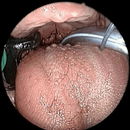

COBLATION Assisted Surgeries

A minimally invasive, low thermal technology for effective dissection and removal of tissue, COBLATION Technology has been used for ENT procedures such as tonsillectomy, turbinate reduction, laryngeal lesion debulking and soft palate.

While conventional electrosurgical devices use high temperatures to remove and cut tissue, our COBLATION Technology creates a controlled, stable plasma field to precisely remove tissue at a low relative temperature, resulting in minimal thermal damage to surrounding soft tissues. Its features include very limited depth of thermal penetration; minimal collateral tissue damage; localised effect; and controlled, volumetric tissue removal. Coblation is often preferred for its ability to reduce surgery duration and pain, minimise bleeding, and speed up recovery times in patients undergoing certain types of surgery.